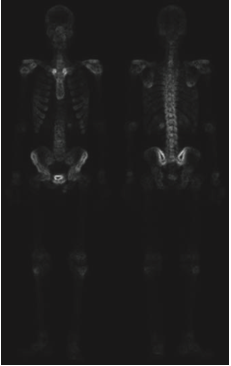

실제로 일반적인 샤프닝 영상에 비해서 훨씬 깔끔한 영상을 얻은 것을 볼 수 있습니다. 하지만 여전히 밝기값이 낮기 때문에 마지막으로 거듭제곱-법칙 변환을 적용해여 아래의 최종 영상을 얻을 수 있습니다.

위의 과정이 의미하는 바는 단일 기법으로는 가능하지 않은 결과를 얻기 위해서 결합될 수 있는 프로세스들이 있음을 의미합니다. 이때 어떤 프로세스들을 결합할 지는 어떤 문제를 해결하느냐에 달라지게 됩니다.